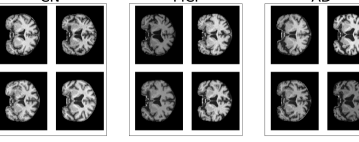

Figure 1: Comparison of the spatially normalized MRI scans of 4 subjects in each of the CN, MCI, and AD categories. To the human eye, distinguishing the difference across the disease stages is a difficult task.

3. Difficulty in distinguishing the visual difference of a brain in the different Alzheimer’s stages. Human brains are distinct by nature, and the quality of MRI collections from different clinical settings add to the noise level of the data. In Figure 1, we plotted out the brains of subjects in CN/MCI/AD, and show that the difference in anatomical structure from CN to MCI to AD is very subtle.